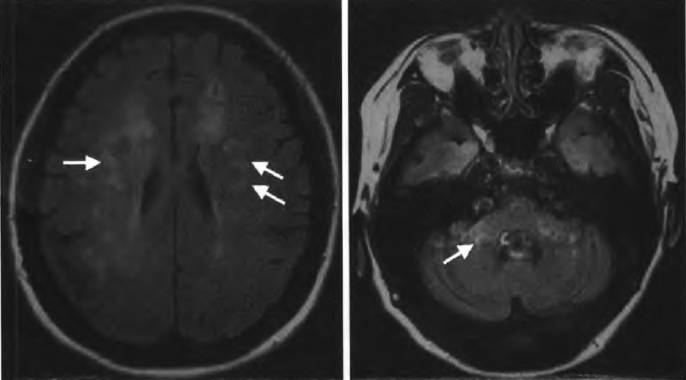

脑萎缩核磁共振图片

脑萎缩核磁共振图片,脑萎缩ct图片